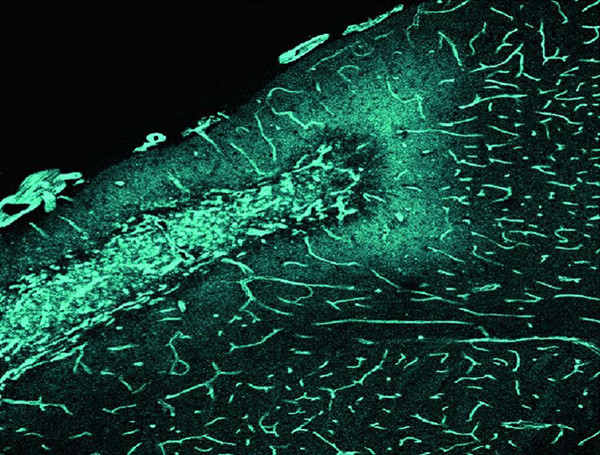

圖說:ADAMTS13調(diào)控腦卒中后血管新生和重塑的關(guān)鍵步驟。染色小鼠腦切片顯示腦卒中引起大腦皮層缺血巢周邊區(qū)域血管新生,然而新生的血管尚不成熟和穩(wěn)定。給予小鼠重組ADAMTS13不但增加新生血管的數(shù)量并且可促進(jìn)血管的功能重塑,最終導(dǎo)致小鼠神經(jīng)功能的修復(fù)。

近年,血管新生對腦卒中損傷的修復(fù)作用受到廣泛的關(guān)注。新生血管一方面可以改善腦血流和腦內(nèi)微環(huán)境,另一方面通過分泌神經(jīng)營養(yǎng)因子和趨化因子等,促進(jìn)神經(jīng)干細(xì)胞的增殖和存活。臨床證據(jù)也顯示,腦組織中微血管的多少與腦卒中患者的預(yù)后密切相關(guān)。腦科學(xué)研究院趙冰樵教授研究團(tuán)隊(duì),采用活體小鼠腦血管多光子顯微鏡實(shí)時(shí)動態(tài)成像等先進(jìn)技術(shù),發(fā)現(xiàn)敲除ADAMTS13基因后,小鼠在腦卒中恢復(fù)期時(shí)血腦屏障的破壞更加嚴(yán)重,血管內(nèi)大分子物質(zhì)的血管外滲漏更多,從而導(dǎo)致血管周細(xì)胞以及平滑肌細(xì)胞覆蓋率下降,最終造成腦毛細(xì)血管、灌注血管減少,表明ADAMTS13是參與血管新生和功能重塑的關(guān)鍵分子。在敲除ADAMTS13基因的基礎(chǔ)上,研究人員敲除了另一個(gè)基因VWF,結(jié)果發(fā)現(xiàn)這些小鼠的血腦屏障破壞和滲漏明顯減輕。通過病毒和藥物干預(yù)等手段,他們進(jìn)一步證明ADAMTS13的作用機(jī)制是通過VWF作用于微血管內(nèi)皮細(xì)胞的Gal-3以及Weibel-Palade小體中的Ang-2,進(jìn)而引起血管內(nèi)皮細(xì)胞生長因子VEGF受體2磷酸化。

研究人員隨后使用藥物“重組ADAMTS13”增加小鼠體內(nèi)的ADAMTS13含量,發(fā)現(xiàn)這些小鼠腦內(nèi)確實(shí)形成了更多和更加成熟的毛細(xì)血管,而小鼠的感覺和運(yùn)動功能也得到了顯著的改善。該研究首次證實(shí)了ADAMTS13是調(diào)控腦卒中后血管新生、成熟和功能重塑的重要分子。研究人員認(rèn)為進(jìn)一步了解血管新生和功能重塑的調(diào)控因素并加以針對性治療,將有助于恢復(fù)腦卒中患者受損的神經(jīng)功能。